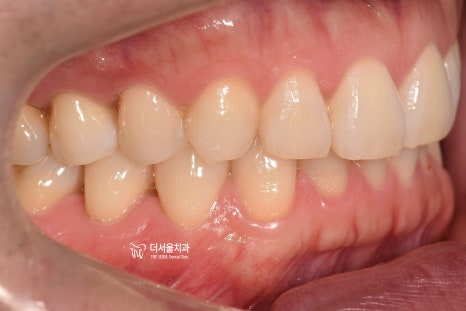

『1. 치아 상태 확인』

정면, 측면, 교합면 등 여러가지 방향에서

환자가 가지고 있는 치열의 상태를 먼저 확인합니다.

삐뚤빼뚤한 곳은 있는지, 또는 거꾸로 물리는 곳은

없는지, 나아가 충치 및 염증을 가지거나

치아 이동에 방해가 될 수 있는 사랑니를

가지고 있는지, 결손치나 있는지 등을

면밀하게 살펴보게 됩니다.